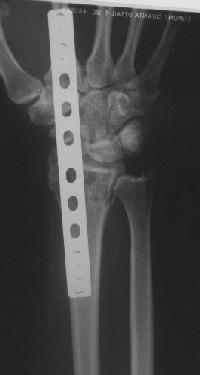

Clinical Example: Distraction plate fixation of distal radius fracture

distal radius fracture

distraction plate